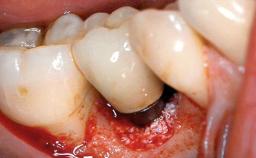

A 77-year-old male patient was referred for the management of frequent and repeated acrylic fracture of his existing mandibular fixed full-arch implant-supported metal/acrylic prosthesis. He also complained about softtissue soreness and the lack of retention and stability of his maxillary removable partial metal/acrylic prosthesis. Both prostheses had been delivered two years previously as part of his full-mouth rehabilitation (caries, tooth wear, tooth fracture). His medical history revealed high blood pressure, controlled with the use of antihypertensive medication.